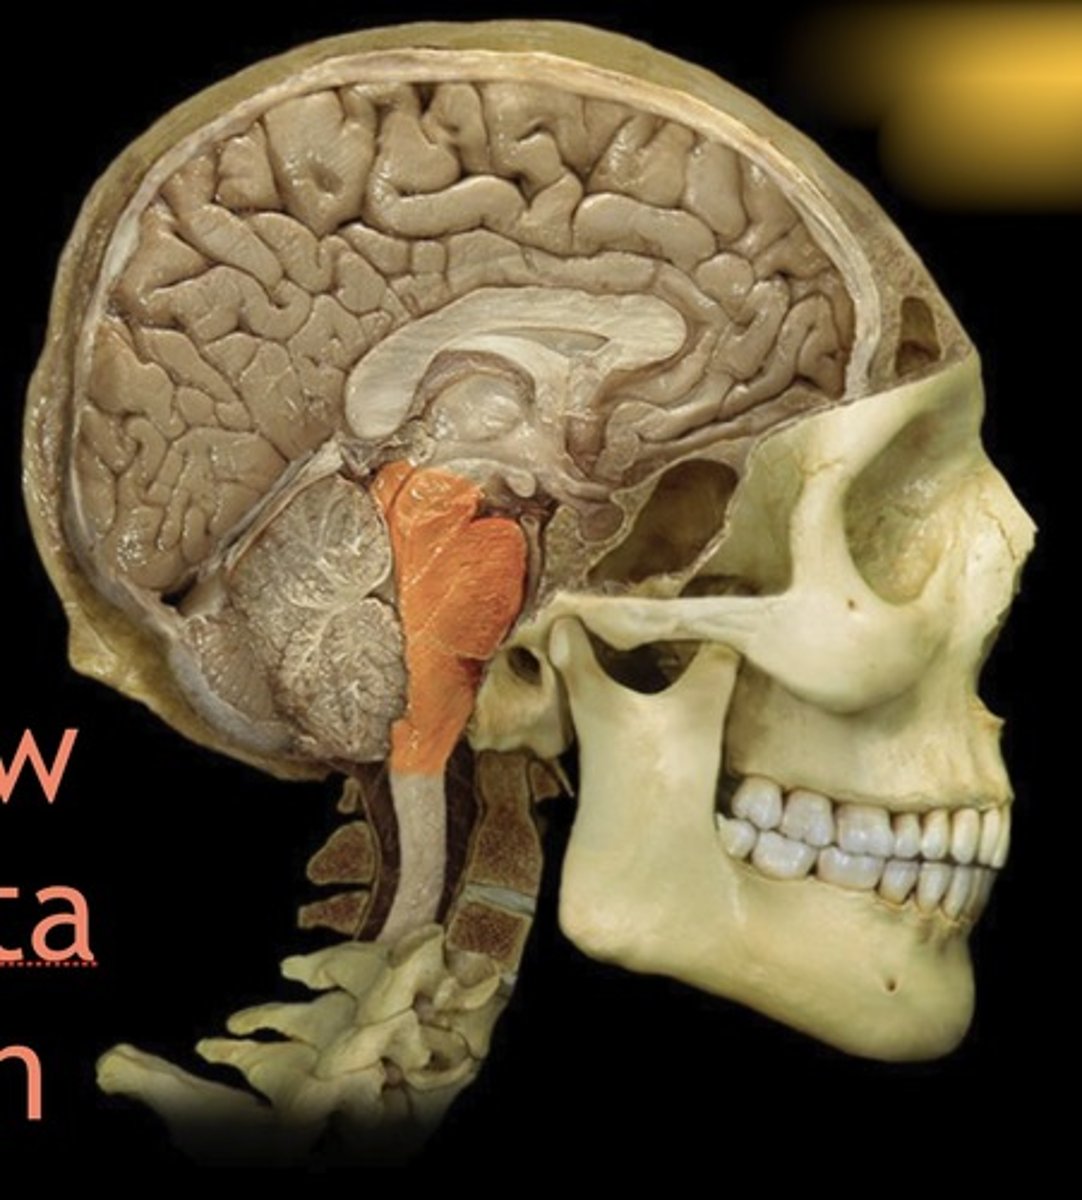

brainstem

Name this structure

Midbrain

Name this structure

Pons

Name this structure

Medulla Oblongata

Name this structure

Cerebral aqueduct

Name this structure

Cerebral crus

Name this structure

Cerebral Peduncle

Name this structure